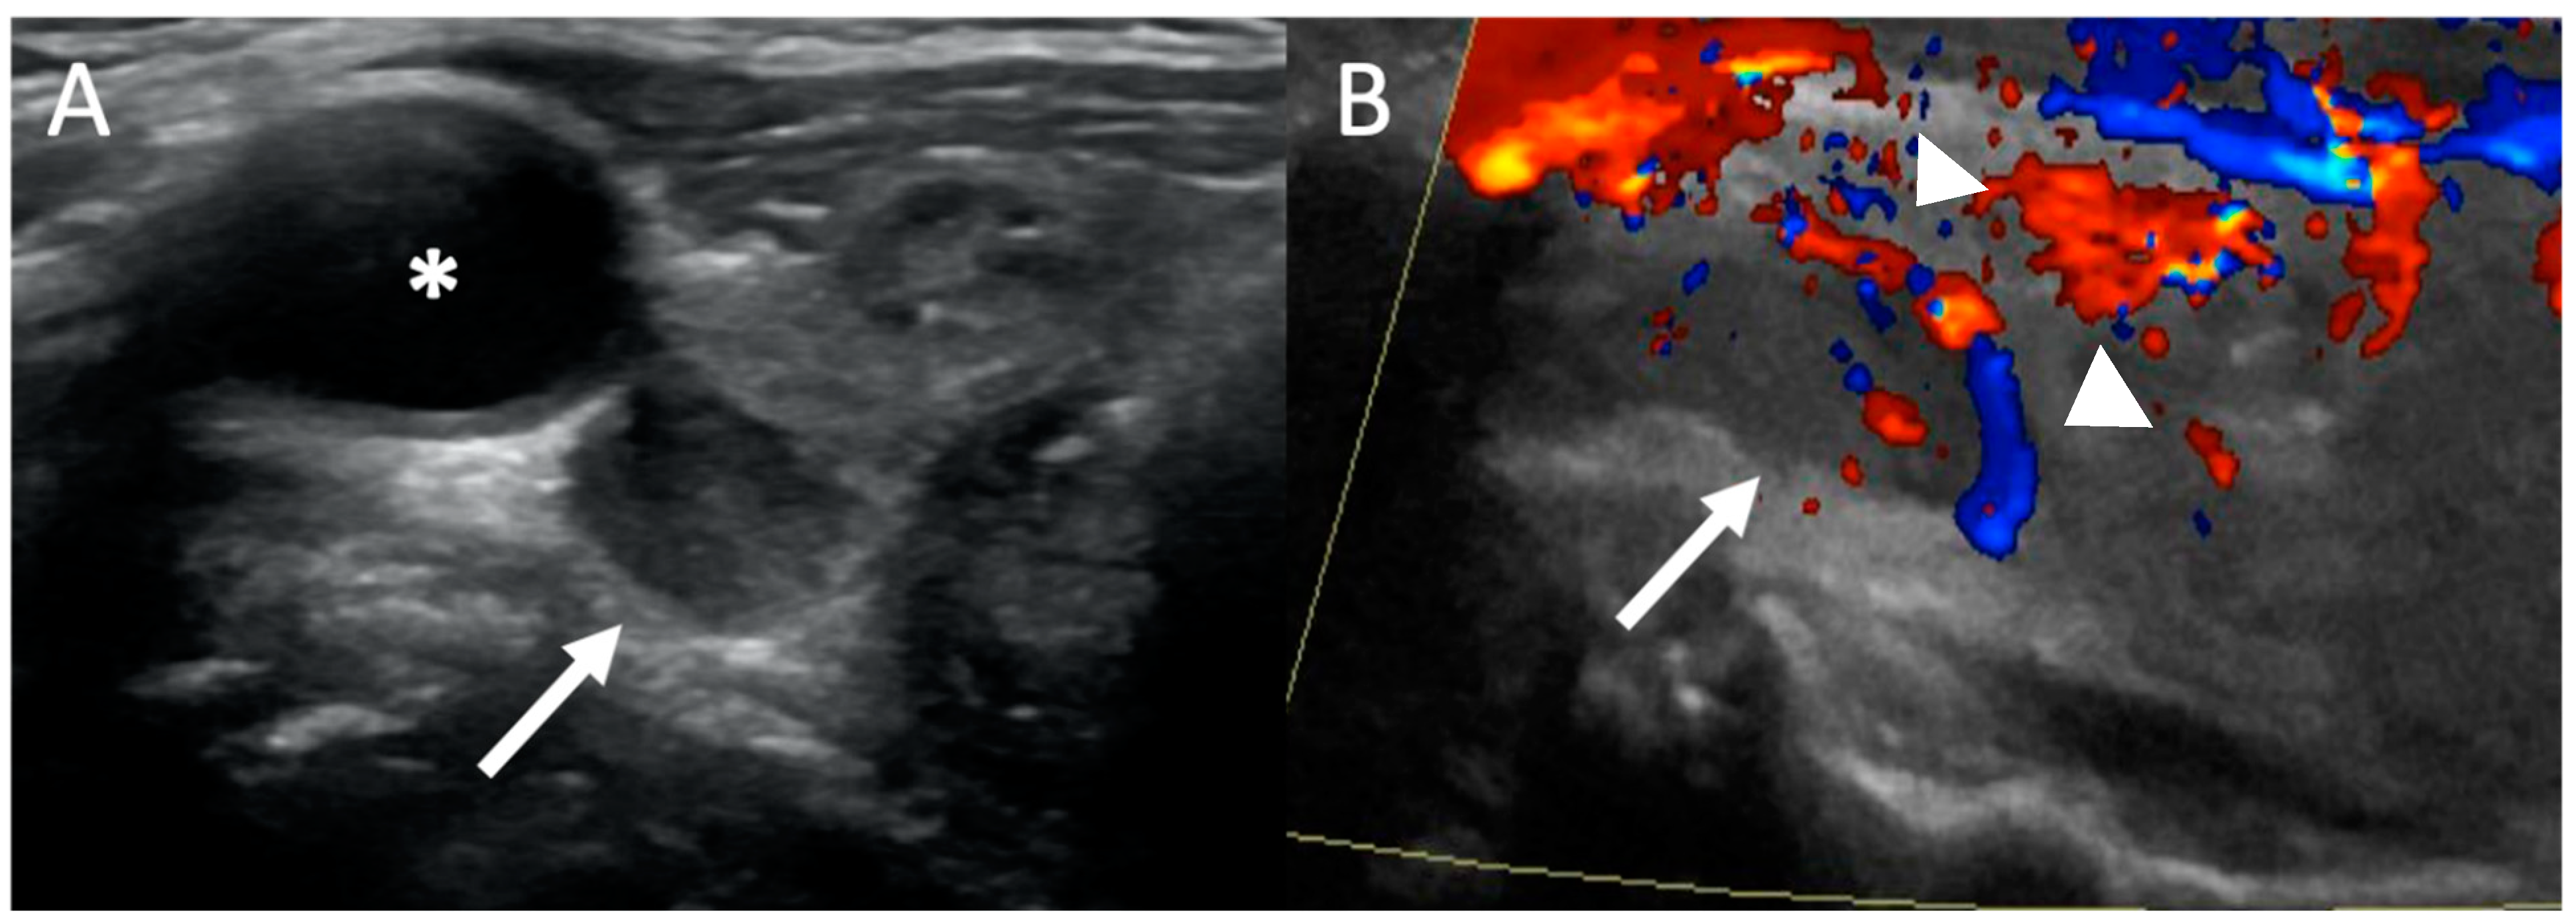

- Wolf, R.J.; Cronan, J.J.; Monchik, J.M. Color Doppler sonography: An adjunctive technique in assessment of parathyroid adenomas. J. Ultrasound Med. 1994, 13, 303–308. [Google Scholar] [CrossRef]

- Mohammadi, A.; Moloudi, F.; Ghasemi-Rad, M. The role of colour Doppler ultrasonography in the preoperative localization of parathyroid adenomas. Endocr. J. 2012, 59, 375–382. [Google Scholar] [CrossRef] [PubMed]